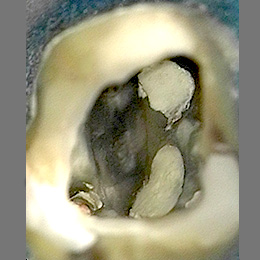

Fallbeispiel: Molarenrevision mit Seitenkanal

Werden im Rahmen einer Wurzelkanalbehandlung nicht alle Bereiche innerhalb des Wurzelkanalsystems ausreichend gereinigt, kann es zu persistierenden Infektionen kommen. In diesem Fall war die persistierende Infektion auf einen feinen Seitenkanal zurückzuführen – mit einer Revisionsbehandlung und gründlicher Reinigung des Wurzelkanalsystems können auch solche persistierenden Infektionen erfolgreich behandelt werden!